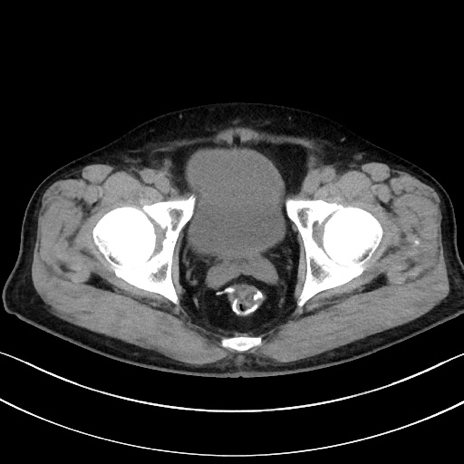

症例15(横断像)

【症例】70歳代男性

【主訴】腹痛

【現病歴】今朝から腹痛あり。全体的に痛い。特に左上の方。排ガスが今日はない。冷や汗が出る。

【既往歴】直腸癌術後

【身体所見】左側腹部〜上腹部に圧痛あり。腹膜刺激症状明らかなではない。軽度反跳痛。左下腹部に術後瘢痕あり。

【データ】WBC 7700、CRP 0.02